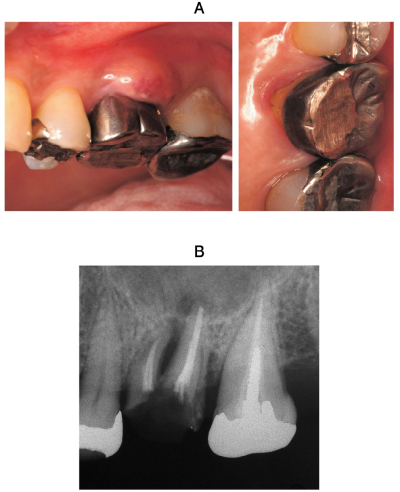

59歳の女性。上顎左側第一大臼歯の歯肉腫脹を主訴として来院した。1週前に食事中に激痛があり、その後歯肉が腫脹してきたという。初診時の口腔内写真と補綴装置除去後のエックス線写真を別に示す。

適切な治療はどれか。1つ選べ。